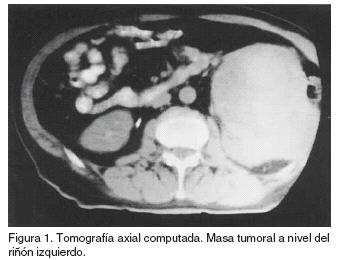

TAC - Rim hidronefrótico, não funcionante com litíase ...

TAC - Rim hidronefrótico, não funcionante com litíase ... from www.researchgate.net